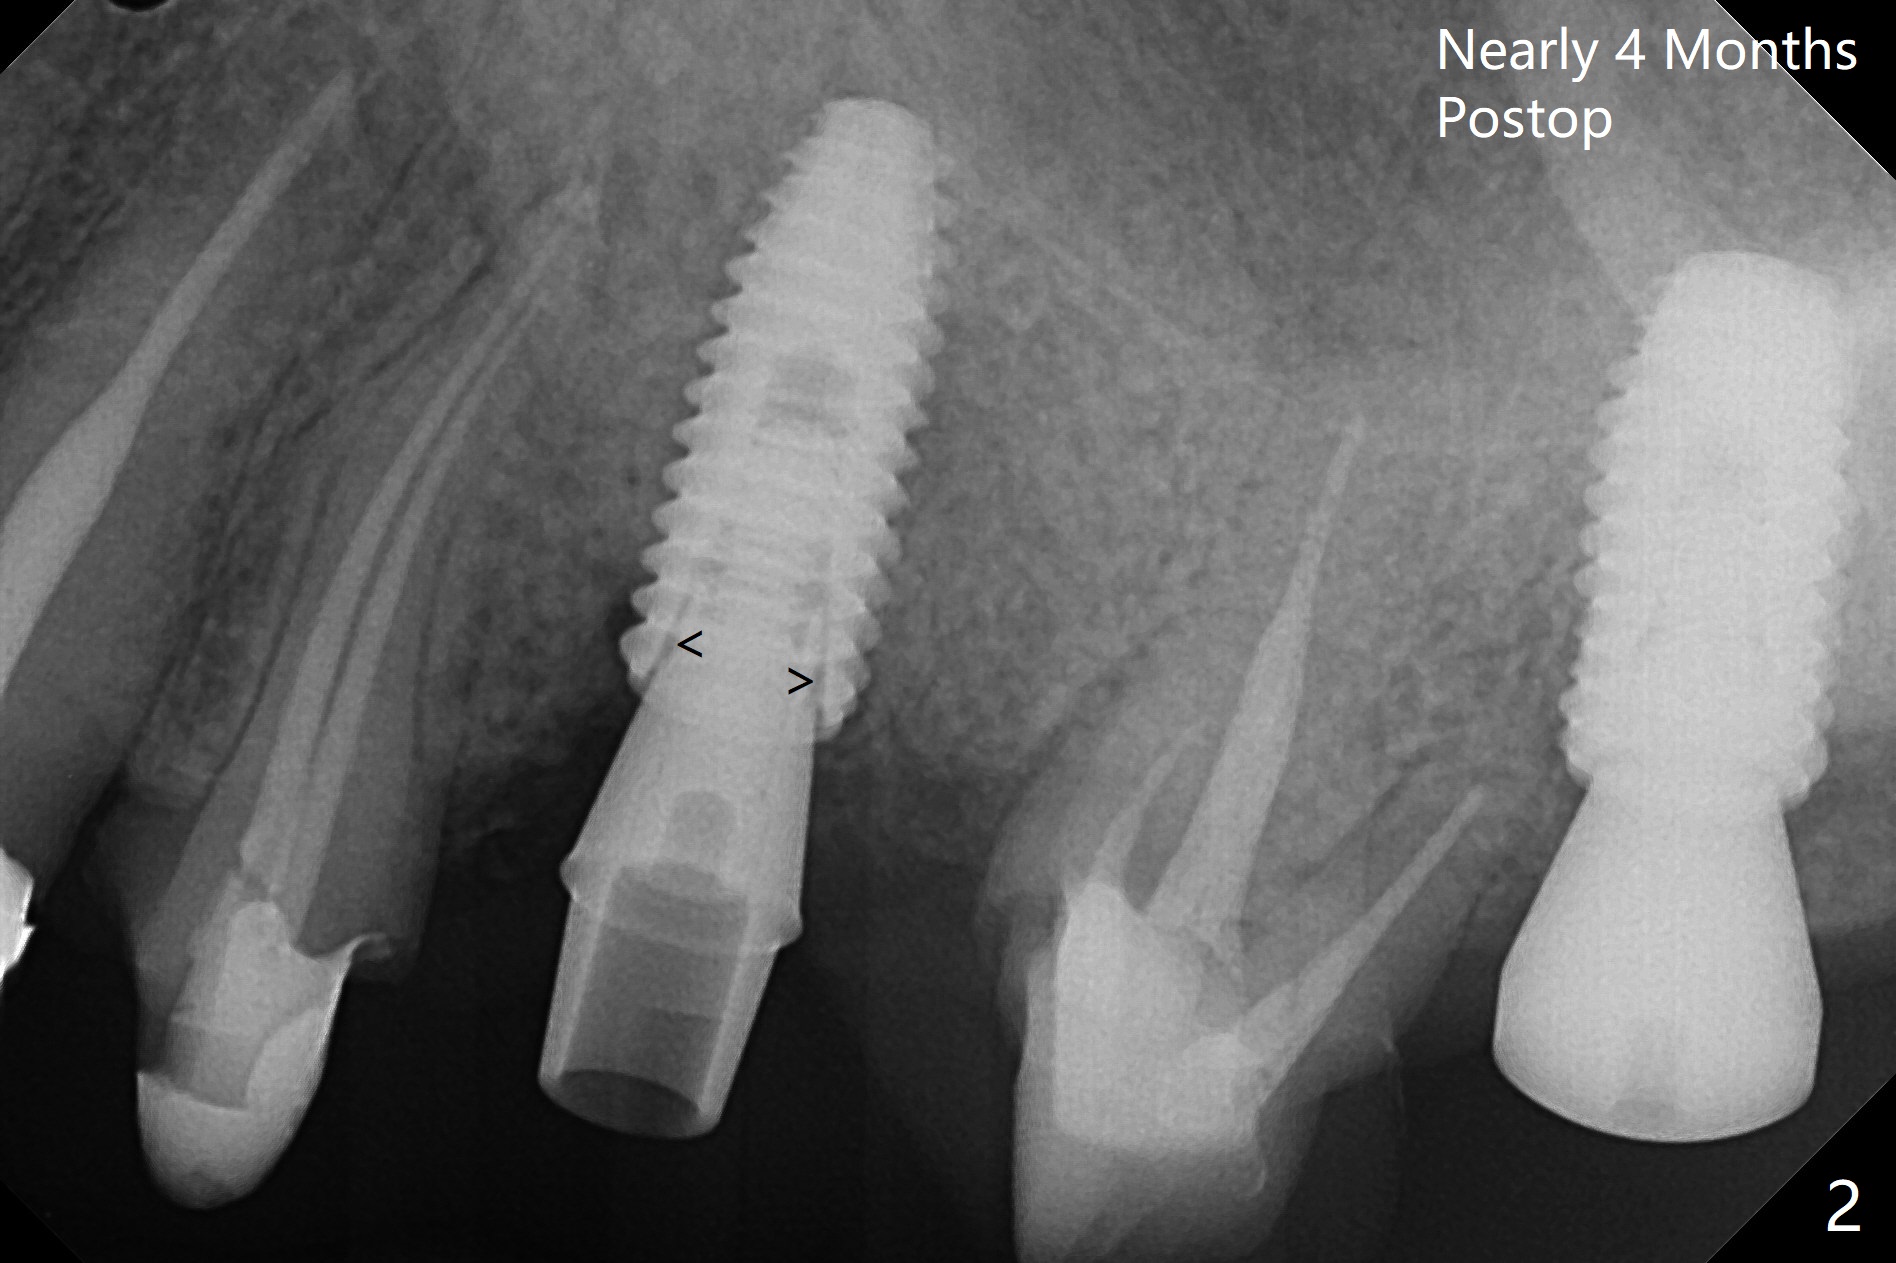

After underdrilling (3.5x14.5 mm drill (10.5 mm offset), a 4.5x11.5 mm implant is unable to enter the osteotomy at #13; following use of 4x10 mm drill (partial normal drilling), the implant is inserted smoothly with insertion torque ~ 35 Ncm. Sticky bone is placed in the bony portion of the buccal gap, while 2 pieces of PRF membrane in the gingival portion of the buccal gap. The bone density at #15 is low, the insertion torque is ~15 Ncm with normal drilling without cortical tap (Fig.1). The procedure is smooth in part due to no sinus involvement (red dashed line). An immediate provisional FPD is fabricated for #12-14. But local oral hygiene is difficult to maintenance. When the wound heals at #13, the FPD is removed. The bone loss is minimal nearly 4 months postop; the abutment at #13 is incompletely seated (Fig.2 arrowheads: gap). After repositioning, the abutment is re-seated completely without gap (arrowheads); a 5.7x4(3) mm cemented abutment is placed at #15 (Fig.3,4). Four crowns are cemented 4 months 10 days postop (Fig.5).